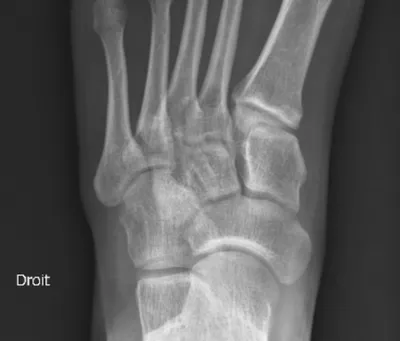

- Permet de rechercher une fracture.

- Permet de rechercher une arthrose ou une arthrite.

- Permet de rechercher des calcifications des tissus mous.

- Permet de visualiser la plupart des tumeurs osseuses bénignes ou malignes.